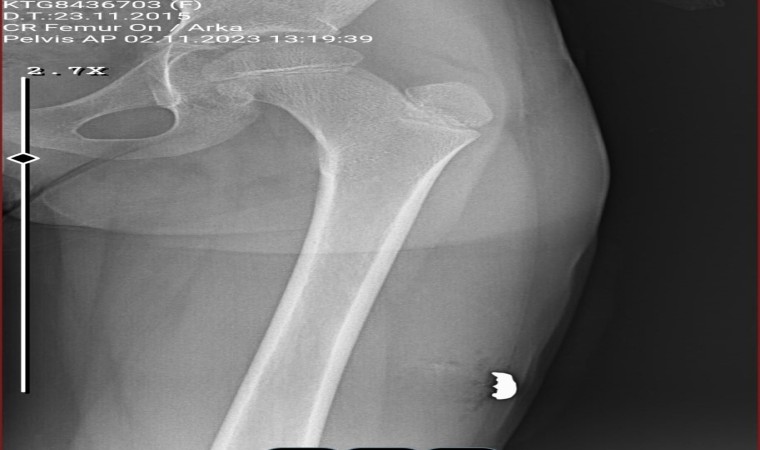

Bacağındaki kurşun çıkartıldı

Kavgada hiçbir suçu yokken sol bacağına isabet eden kurşunla yaralanan 8 yaşındaki Sinem Uça ise Antalya Eğitim Araştırma Hastanesi’nde tedavi altına alındı. Burada operasyon geçiren Sinem’in baldır kısmından giren kurşun çıkartıldı. Yaklaşık 6 saatlik tedavinin ardından küçük kız taburcu olup evine gönderildi.